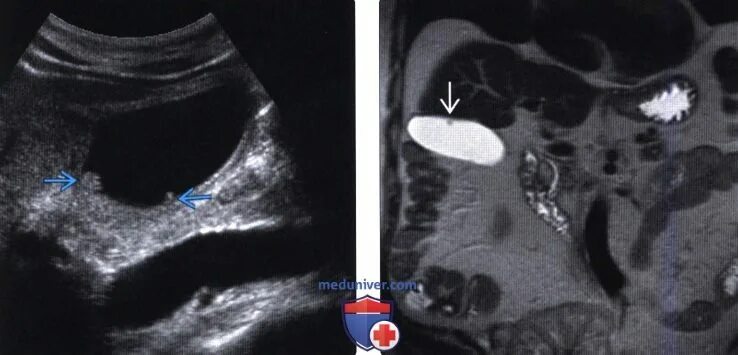

Может ли полип в желчном